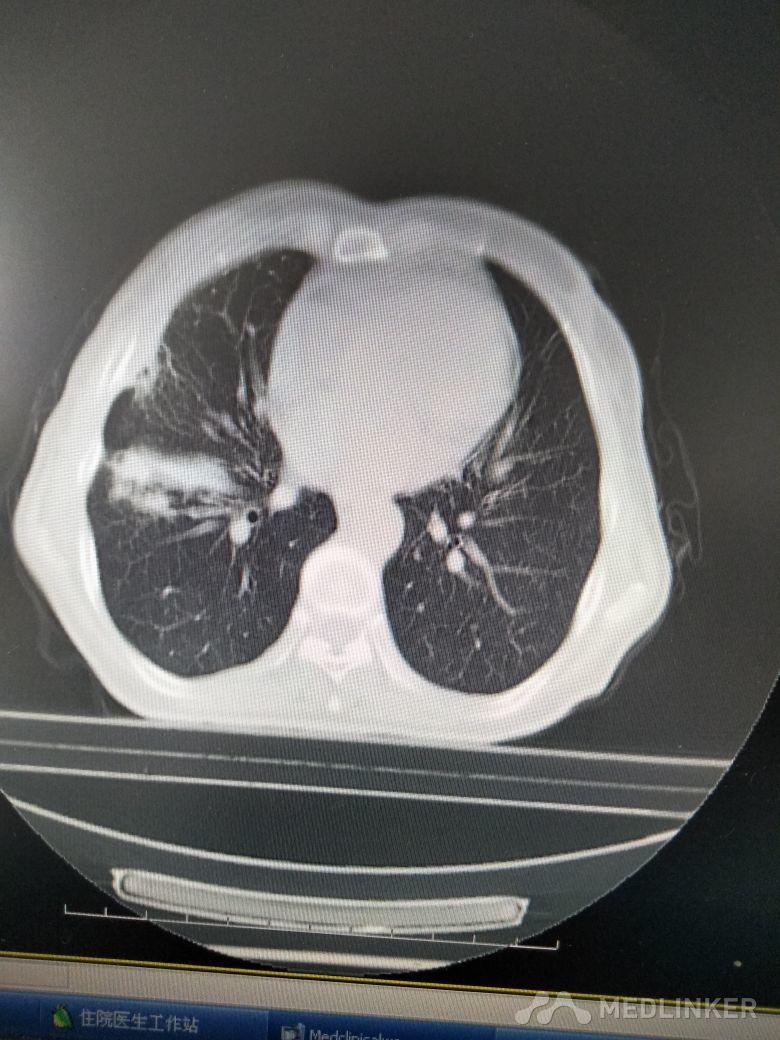

病史: 患者咳嗽、咳痰1月,右侧胸痛,无明显乏力,无发热,食欲可。来院拍胸cT示右肺片状密度增高影,边界不清,密度较均匀。考虑肺炎,给予抗炎治疗半月,症状加重。予抗结核治疗7天,胸痛明显缓解,咳嗽、咳痰减轻。